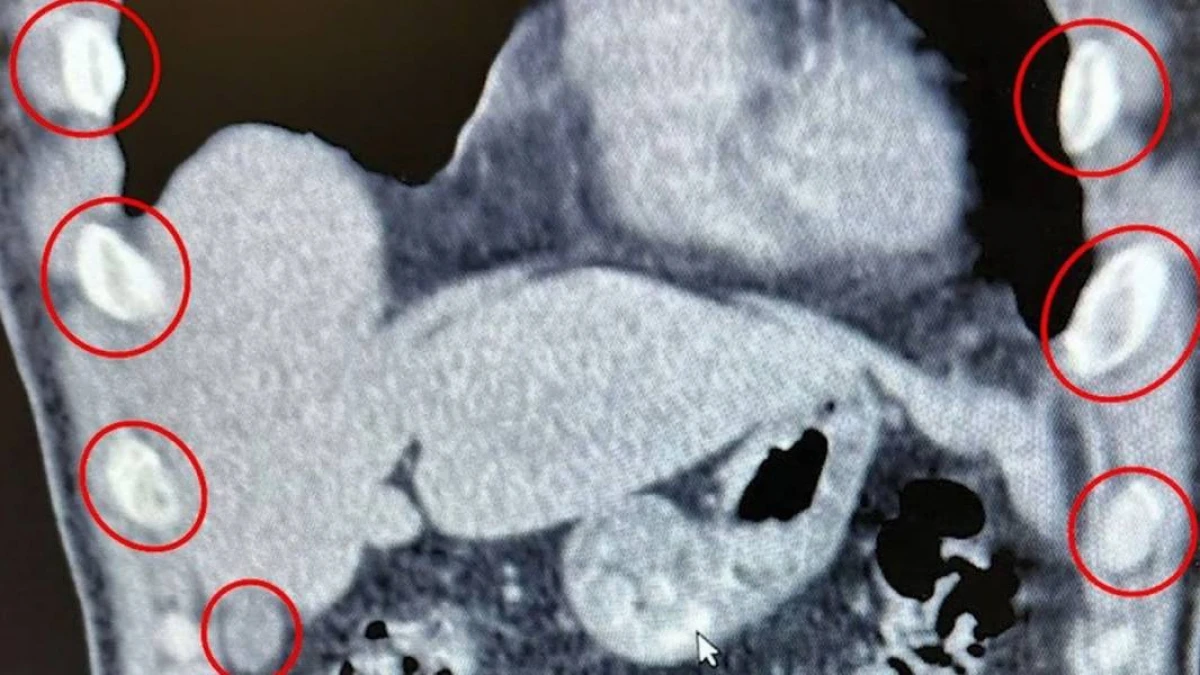

İki şəxsin mədəsindən 136 kapsul narkotik tapıldı

Bitlis İl Təhlükəsizlik Müdirliyi narkotiklərlə mübarizə əməliyyatı keçirib.TodayPress TV "Haber Global"a istinadən xəbə...